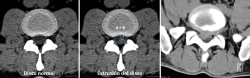

La TAC visualiza con bastante precisión el tejido óseo, siendo claramente superior a la RM para ello. También permite visualizar los tejidos blandos intra- y paraespinales, aunque la RM es muy superior en la evaluación de estos tejidos, por lo que está siendo desplazada por esta para el estudio de los problemas discales, degenerativos y radiculomedulares (Figura 11).

Figura 12. Tomografía axial computarizada de hernia discal. Reproducido de Gaillard(26).

Entre las principales indicaciones de la TAC, se incluirían la sospecha clínica de hernia discal (Figura 12)(26), la estenosis del canal vertebral lumbar, la fractura vertebral lumbar, los tumores vertebrales, la valoración posquirúrgica tras una cirugía de artrodesis vertebral lumbar y la sospecha de una sacroileitis en el contexto clínico de una posible espondiloartropatía inflamatoria. También es muy útil como herramienta auxiliar en determinados procesos diagnósticos, como por ejemplo en la biopsia de una zona sospechosa y en el diagnóstico postoperatorio de la correcta colocación de implantes en la columna vertebral.

Al igual que en la radiología simple, muchos pacientes asintomáticos presentan imágenes anormales en la TAC. En el estudio de Wiesel et al.(25), más del 35% de las TAC de columna lumbar en personas asintomáticas eran patológicas. Por ello, los expertos advierten de la necesidad de correlacionar adecuadamente los hallazgos de la TAC con la sintomatología referida por el paciente.

La sobrevaloración de las imágenes sin una correcta valoración clínica puede conducir a errores diagnósticos y terapéuticos de importancia, oscilando desde restricciones severas de la actividad física y laboral, indicaciones terapéuticas o rehabilitadoras inadecuadas, y hasta intervenciones quirúrgicas no indicadas.